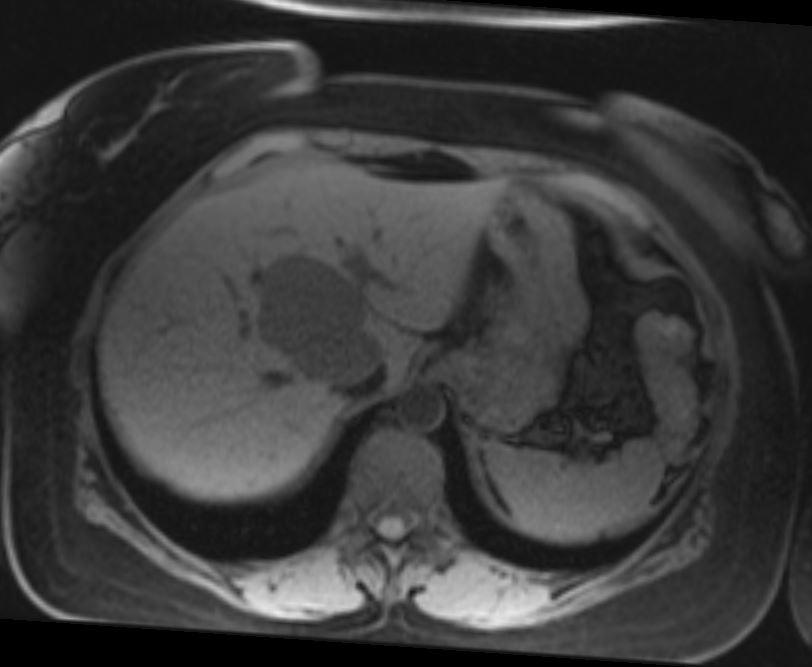

Case of the Week 28 2017 What is the most likely diagnosis? Answer Answer: Cavernous Liver Hemangioma Kategori:Cases Önceki yazı Case of the Week 25 2017 Sonraki yazı Case of the Week 29 2017